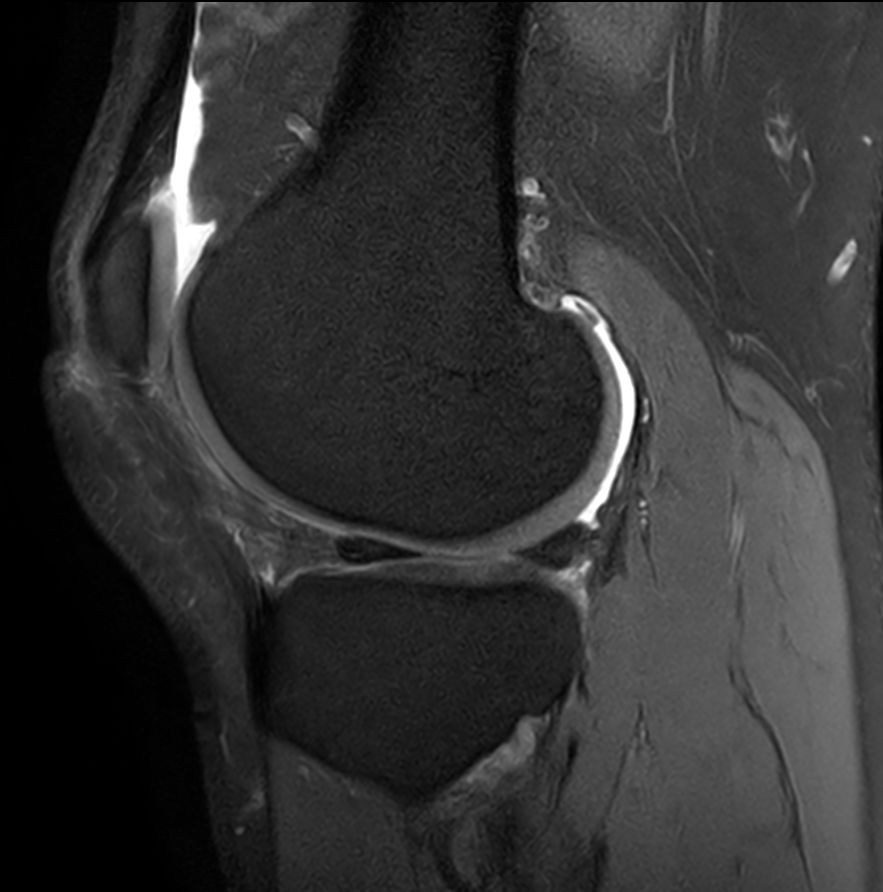

Sagittal PDw SPAIR - Compressed SENSE